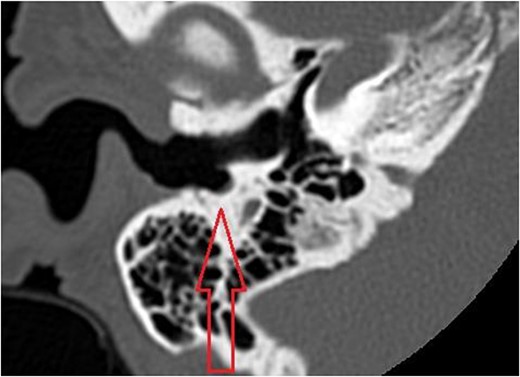

The patient evaluation and the data collection of this rare entity were performed in the senior author’s Otolaryngology practice in Poplar Bluff Regional Medical Center, Poplar Bluff, Missouri, USA (Table 1). Patient A, a 72-year-old female, was initially seen in 06/2015 and has been consistently followed for 87 months. On initial evaluation, the unusual clinical presentation triggered a workup with a CT of the temporal bone (Fig. 1), revealing a minor area of cortical erosion in the inferior wall of her right bony external auditory canal. Her initial presenting complaint was cerumen impaction on the right side associated with same side hearing loss. The patient has no history of diabetes, is treated with estradiol and progesterone tablets for hormonal replacement therapy and has no diagnosis of osteoporosis. Her blood pressure medications include atenonol and triamteren and has been on the same medications for the last seven years of our observation. The patient was managed with serial external auditory canal debridements, every 6 months. She had no history of otitis externa during the years of follow-up. Photographic documentation in her most recent visit (10/2022) revealed healthy appearing healthy mucosalization of the cavity and minimal amount of ceruminous debris (Fig. 2).

Axial cut in the inferior aspect of the external auditory canal in patient A (CT of the temporal bone) demonstrating the indentation of the inferior aspect of the external auditory canal.